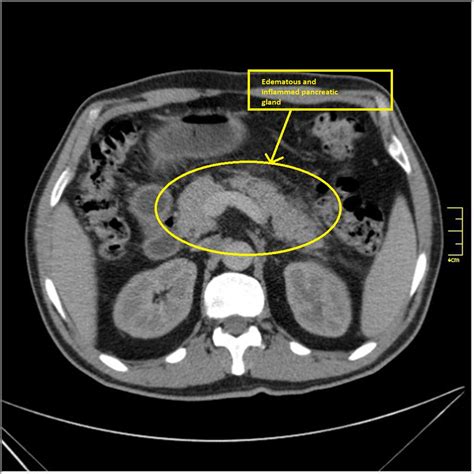

Pancreatitis is an inflammation of the pancreas that can be acute or chronic. CT scans are essential in diagnosing and managing pancreatitis by providing detailed images of the pancreas and surrounding structures. Acute pancreatitis often presents with sudden, severe abdominal pain, while chronic pancreatitis is characterized by persistent inflammation and damage to the pancreas.

CT scans can reveal swelling, changes in texture, and other abnormalities in the pancreas that indicate pancreatitis. They can also assess the severity of the inflammation and detect complications such as pseudocysts or necrosis. This information is crucial for developing an effective treatment plan and monitoring the patient's progress.